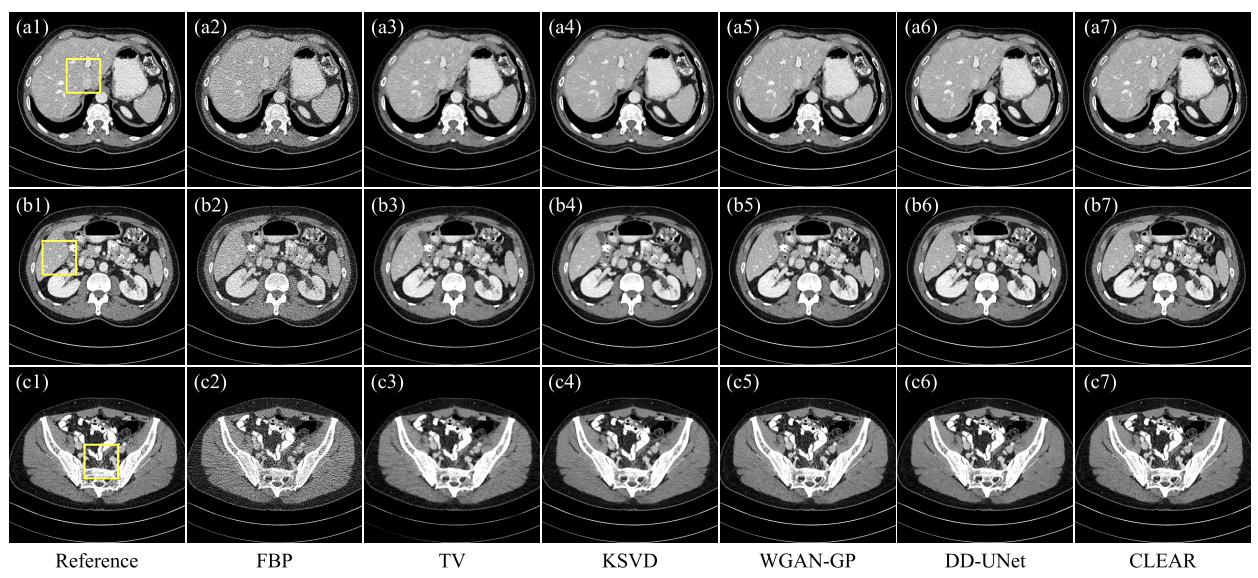

- 비교 모델: FBP, TV(반복 재구성 방법), KSVD(딕셔너리 학습 알고리즘), WGAN-GP(생성 모델을 기반으로 한 후처리 기법), DD-UNet(연속된 네트워크 처리 알고리즘)

- AAPM 결과

- FBP: 노이즈에 의해 심각히 저하

- KSVD:미세한 특징을 거의 복원X(a4)

- TV: 노이즈 억제 잘 하지만, artifact가 미세구조를 손상( c4)

- DD-UNet: 유클리드 거리 최소화로 인해 흐림 효과가 발생

정량적 분석

CLEAR: 가장 낮은 MAE, 높은 SSIM,PSNR